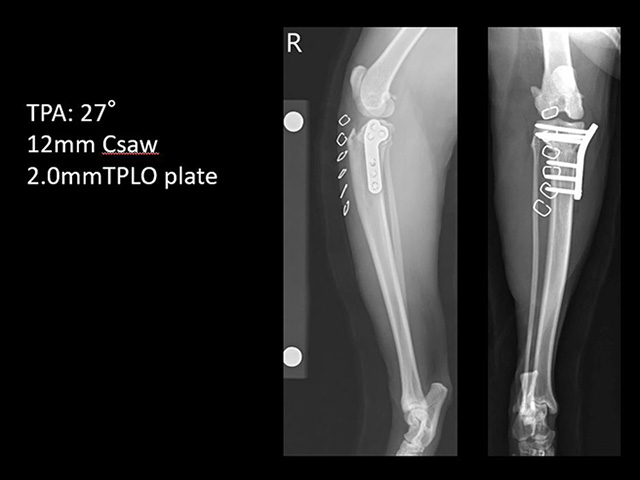

中でもTPLO(Tibial Plateau Leveling Osteotomy; 脛骨高平部水平化骨切術)の成績が良好との研究報告が出され、世界的に広く認知されるようになっています。

本院では、主にTPLOを実施し、ほぼ3週間以内の歩行回復を実現しています。